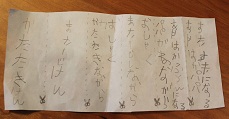

イメージ図にしてみると、

?正常な網膜です。中心部の赤い部分の網膜には、物を見るための視細胞が沢山集まっています。その周りの青にも、視細胞がありますが、赤に比べると数が少なくなります。緑はさらに見え方が落ちる部位です。

?黄斑円孔で、赤の部分の網膜が硝子体に引っ張られて断裂し、無くなってしまうと、視野の中心部が欠損、見たい部分が見えなくなってしまいます。

?手術の効果で、青や緑の網膜を中心部に引き寄せます。

?青の部分の網膜が、視野の中心部の視界を担うようになります。